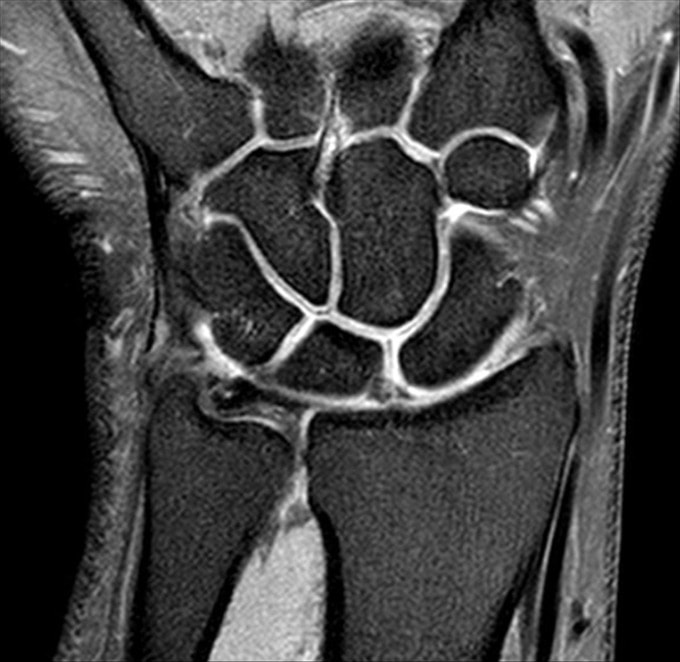

Revisão anatômica de mãos e punhos pela RM

- Mãos e Punhos